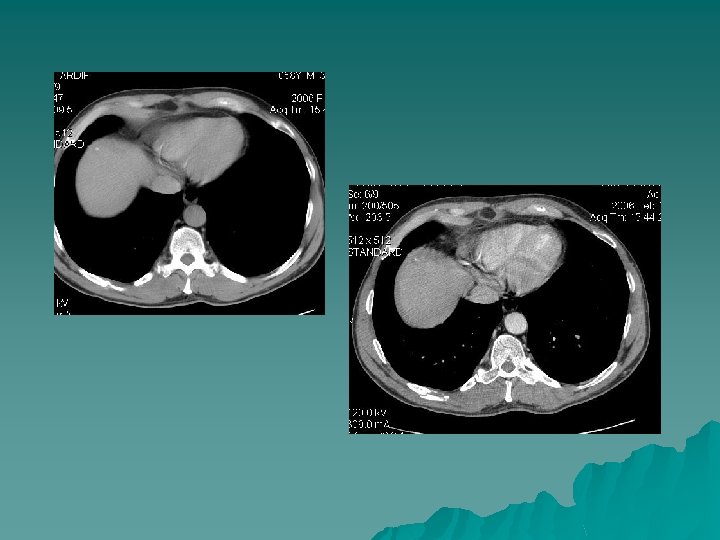

Surveillance d’une patiente traitée par RF pour CHC 12 mois auparavant TDM phase artérielle récidive US PCUS Phase précoce récidive Nodule traité TDM phase portale